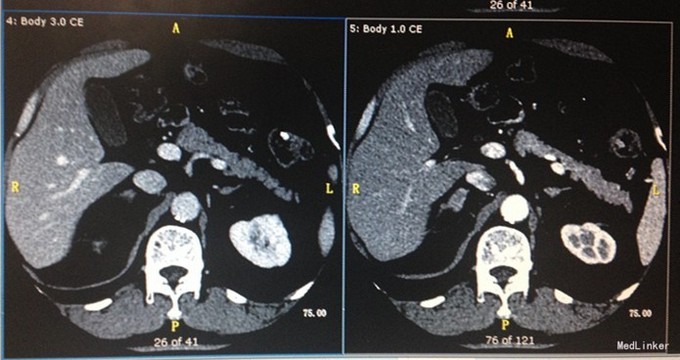

入院查体: BMI:25.39Kg/m2,右下肢活动受限,肌力正常,无畸形,无关节痛,右下肢麻木。 辅助检查:腹部超声:脂肪肝超声所见前列腺内结石或钙化。肾上腺CT:双侧肾上腺占位,请结合临床。左肾囊肿。血脂分析:TG 3.46mmol/L,TC 5.90mmol/L,LDL-C 4.06mmol/L。OGTT及胰岛功能试验未见明显异常。24小时动态心电图:窦性心律/偶发房性早搏、成对房性早搏、短阵房性心动过速/偶发室性早搏、多源室性早搏/ST-T段改变。24小时动态血压:平均血压134/90mmHg,昼夜血压节律异常(非杓型),昼夜血压负荷升高 肾上腺皮质激素系列: 8:00 15:00 24:00 ACTH 15.50 15.45 3.59 COR 386.6 298.1 166.20 肾上腺皮质醇节律及小剂量地塞米松试验 8:00 15:00 24:00 7:00 7:15 ACTH 36.08 14.7 9.08 15.7 17.62 COR 514 284.5 113.5 356 313.3 抑制率:34% 小剂量地塞米松抑制试验(标准法) 8:00 7:00 7:15 COR 241.1 27.17 18.32 ACTH 20.79 2.77 2.49 醛固酮立卧位:(第1、2套) 卧位 立位 卧位 立位 醛固酮 0.11 0.18 0.16 0.17 PRA 0.04 3.2 0.58 5.5 比值 275 5 27 3 醛固酮立卧位(第三套) 卧位 立位 醛固酮 0.14 0.14 PRA 1.4 6.8 比值 10 2.05 卡托普利试验抑制试验: 给药前 1小时 2小时 醛固酮 0.15 0.14 0.14 PRA 9.1 5.6 6.2 比值 116 93 81 试验结果提示未被抑制

诊断:双侧肾上腺占位;高血压;血脂异常症 治疗:拜新同降压,立普妥降脂

住院期间对症给予拜新同控制血压,监测24小时控制血压结果基本正常,后多次院内监测血压结果波动于125-145/80-95mmHg,监测3次血离子血钾均在正常范围,完善各功能试验,虽卡托普利试验未被抑制,但诊断功能性肾上腺肿物证据不足。